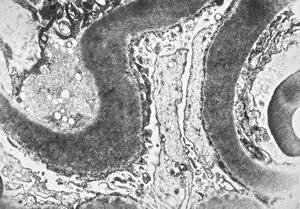

M,6y. | Alport syndrome- digital photo from the screen